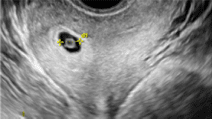

Gestationssæk

Ekkotom, sfærisk struktur omgivet af tyk hyperekkoisk dobbelt ring repræsenterende decidua. Ligger ofte excentrisk i forhold til midtlinien.

Gestationssækken måles ved gennemsnit af minimum 2 diametre af det ekkotomme område vinkelret på hinanden, optimalt medtages diameteren i tværplanet vinkelret herpå.

- GS ses fra dag 33-37 (uge 4+5-5+2)

- Når GS er 10 mm ses blommesæk (som oftest)

- Når GS er 13 mm ses fosterekko (som oftest)

- Når GS er 19 mm ses fosterhjerteblink (som oftest)

Gestationssæk bør ses ved serum-hcg på >2000. (IVF-gravide >2500)